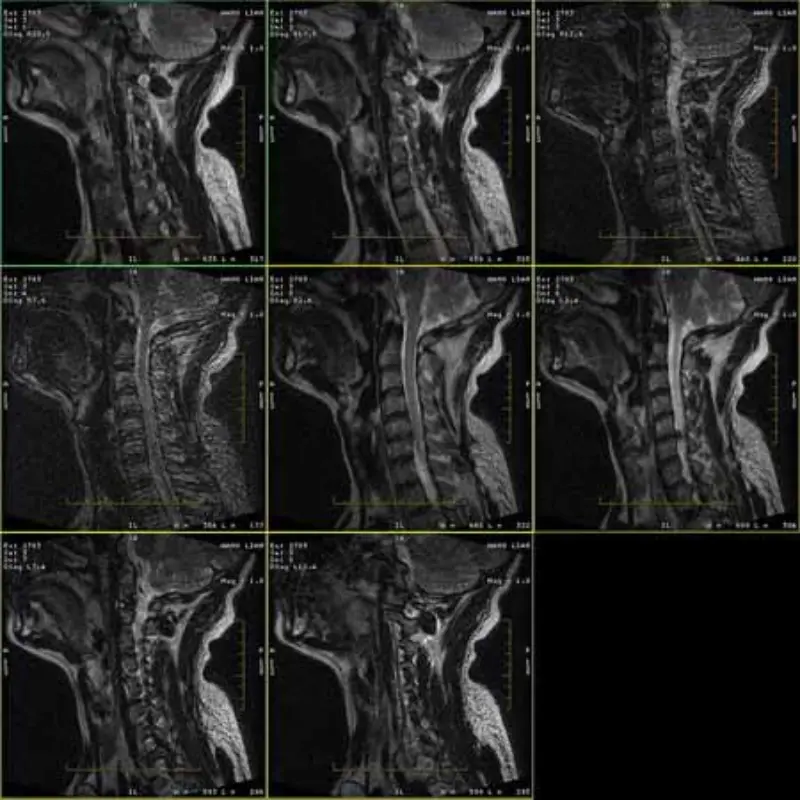

รูปภาพของโปรโตคอล FRFSE และ GRE มีภาพโกสต์ และบางครั้งรูปภาพ SNR ต่ำก็ปรากฏในชุดเดียว แต่ภาพโปรโตคอล SE เป็นเรื่องปกติ

โปรดดูแนบภาพ.